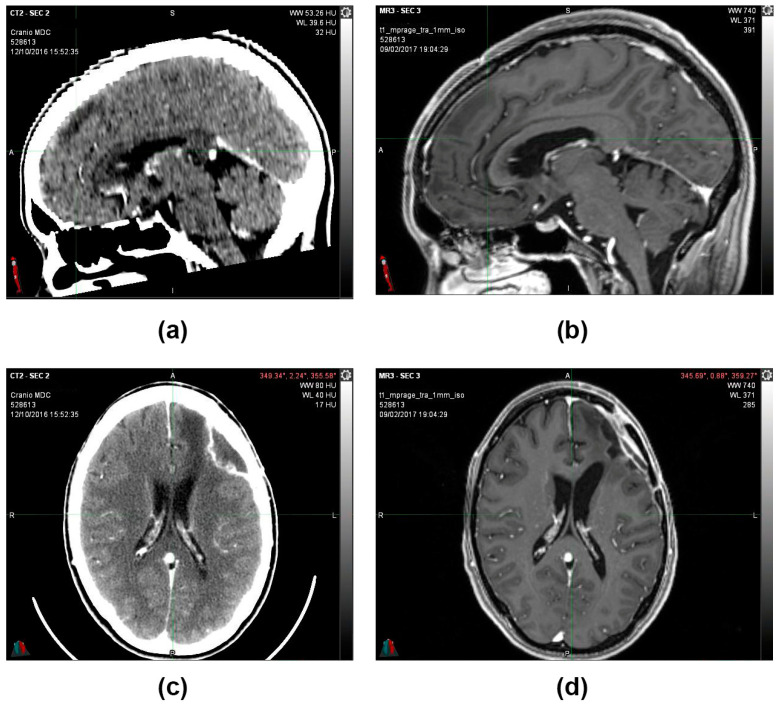

During the follow-up, quarterly visits, clinical-instrumental checks, and monthly blood and biochemistry tests were carried out. At the end of the first cycle of O2O3 therapy (9 February 2017), the 2 cm residual tumor mass that was present 3 months before was no longer visible on the brain magnetic resonance imaging (MRI) (Figure 3), and the stable-negative tumor mass was confirmed with the MRI on 11 October 2022 (Figure 4).